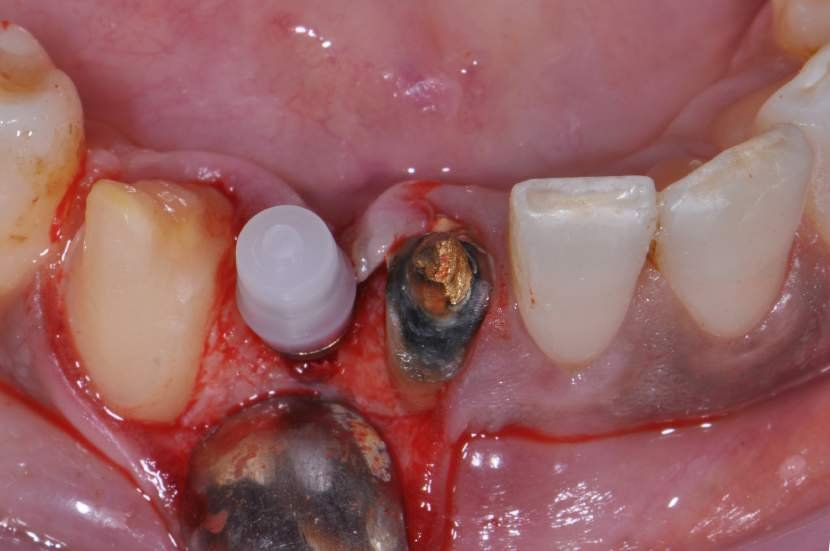

O implante Slim Pilar de corpo único com os diâmetros de 2,5 e 3,0 milímetros (Fig. 2) foram desenvolvidos para superar o desafio de pequenos espaços desdentados.

Um implante de corpo único não tem interface entre o corpo do implante e pilar protético, e, por conseguinte, a perda óssea crestal inicial e ao longo do tempo pode ser reduzida. 5,6

Como o implante perde pouco osso proximal quando posicionado na altura da crista óssea, o implante pode ser colocado tão próximo quanto 1 mm a raiz do dente adjacente.2 Portanto, o espaço mesio-distal um implante de 3,0mm de diâmetro, por exemplo, pode ser tão pequeno como 5,0mm. As principais indicações para os implantes dessas dimensões são: